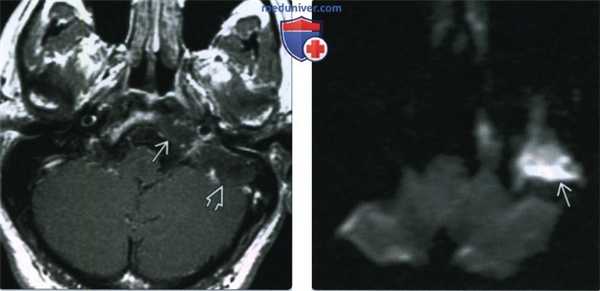

(Слева) При аксиальной КТ височной кости визуализируется врожденная холестеатома, поражающая наружные отделы ската и внутренние отделы сосцевидной части. Экспансивное воздействие на кость подтверждает этот диагноз.

(Справа) При аксиальной МРТ Т2 ВИ у этого же пациента визуализируется гигантская холестеатома сосцевидной части височной кости - хорошо отграниченное гиперинтенсивное объемное образование.

(Слева) При аксиальной МРТ Т1 ВИ С+ у этого же пациента визуализируются оба компонента (латеральный компонент ската и сосцевидный компонент) большой врожденной холестеатомы височной кости. Холестеатома ожидаемо не накапливает контраст.

(Справа) При аксиальной МРТ ДВИ у этого же пациента определяется гиперинтенсивный сигнал в области гигантской врожденной холестеатомы височной кости. Ограничение диффузии - высокоспецифичный признак холестеатомы.